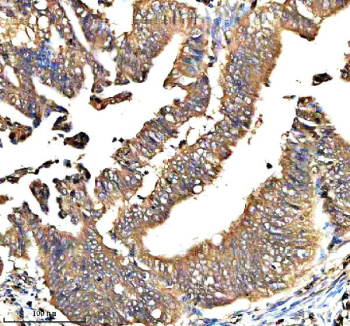

Immunohistochemical staining of QRSL1 using anti-QRSL1 antibody. QRSL1 was detected in a paraffin-embedded section of human colon cancer tissue. Heat mediated antigen retrieval was performed in EDTA buffer (pH 8.0, epitope retrieval solution). The tissue section was blocked with 10% goat serum. The tissue section was then incubated with 2 ug/ml rabbit anti-QRSL1 antibody overnight at 4oC. Peroxidase Conjugated Goat Anti-rabbit IgG was used as secondary antibody and incubated for 30 minutes at 37oC. The tissue section was developed using an HRP secondary and DAB substrate.